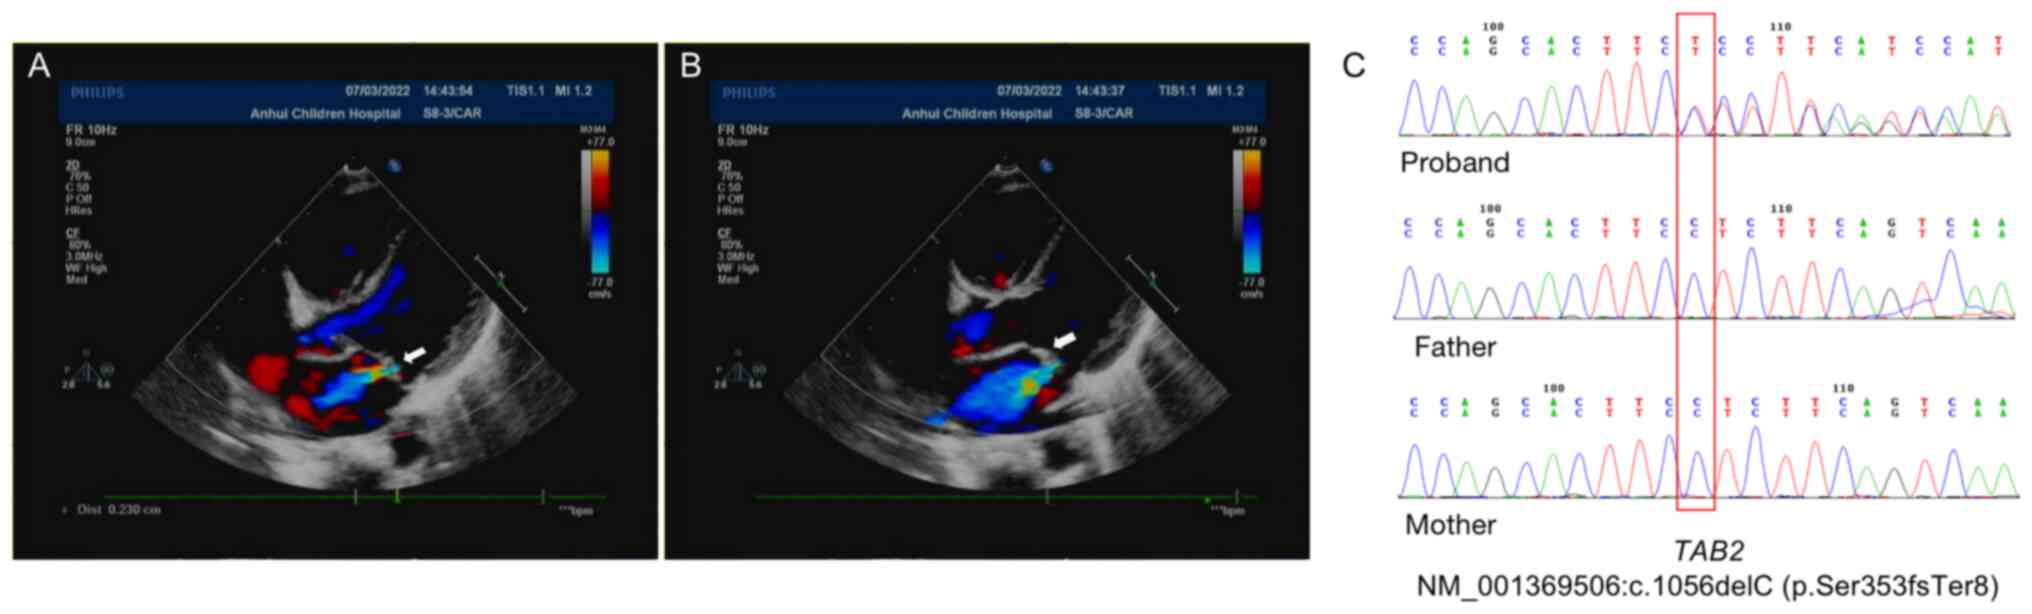

Growth restriction and congenital heart disease caused by a novel TAB2 mutation: A case report

Congenital heart disease (CHD) is a malformation present from birth caused by the abnormal development of the heart and large blood vessels during the prenatal development. The TGF‑β activated kinase 1 (MAP3K7) binding protein 2 (TAB2) gene plays an important role in the embryonic development of heart tissue. When haploid dosage is insufficient, it can lead to CHD or cardiomyopathy. The present study reported a case study of a Chinese child with growth restriction and CHD. The results of whole exome sequencing suggested that a novel frameshift mutation (c.1056delC/p.Ser353fsTer8) occurred in TAB2. The parents of this patient are wild‑type at this locus; therefore, it may be a de novo mutation. The mutant plasmid was constructed in vitro, and the western blotting results showed that the mutation may cease protein expression. This indicated the pathogenic harmfulness of this mutation. In conclusion, the present study emphasizes that TAB2 defects should be investigated in patients with unexplained short stature and CHD, irrespective of family history regarding CHD or cardiomyopathy. The current study provided new data on the mutation spectrum and provided information for second pregnancies and genetic counseling of the parents of patients.